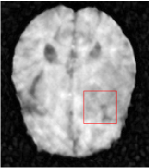

In this section, we test the generalizability of the proposed model that tests on unseen tasks. We fix the well-trained task-invariant parameter and only train for sampling ratios 15%, 25% and 35% with radio masks and sampling ratios 10%, 20%, 30% and 40% with Cartesian masks. In this experiment, we only used 100 training data for each CS ratio and apply a total of 50 epochs. The averaged evaluation values and standard deviations are listed in Table 5.4 and 5.4 for reconstructed T1 and T2 brain images respectively that proceed with radio masks, and Table 5.4 shows the qualitative performance for reconstructed T2 brain image that applied random Cartesian sampling masks. In T1 image reconstruction results, meta-learning improved 1.6921 dB in PSNR for 15% CS ratio, 1.6608 dB for 25% CS ratio, and 0.5764 dB for 35% comparing to the conventional method, which in the tendency that the level of reconstruction quality for lower CS ratios improved more than higher CS ratios. A similar trend happens in T2 reconstruction results with different sampling masks. The qualitative comparisons are illustrated in Figure 2, 4 and 5 for T1 and T2 images tested in skewed CS ratios in radio masks, and T2 images tested in Cartesian masks with regular CS ratios respectively. In the experiments that conducted with radio masks, meta-learning is superior to conventional learning especially at CS ratio 15%, one can observe that the detailed region in red boxes keeps edges and is more close to the true image, while conventional method reconstructions are hazier and lost details in some complicated tissue. The point-wise error map also indicates that Meta-learning has the ability to suppress noises.

Training with Cartesian masks is more difficult than radio masks, especially for conventional learning where the network is not very deep since the network only applied three convolutions each with four kernels. Table 5.4 indicates that the average performance of meta-learning improved about 1.87 dB comparing to conventional methods with T2 brain images. These results further demonstrate that meta-learning has the benefit of parameter efficiency, the performance is much better than conventional learning even if we apply a shallow network with small size of training data.